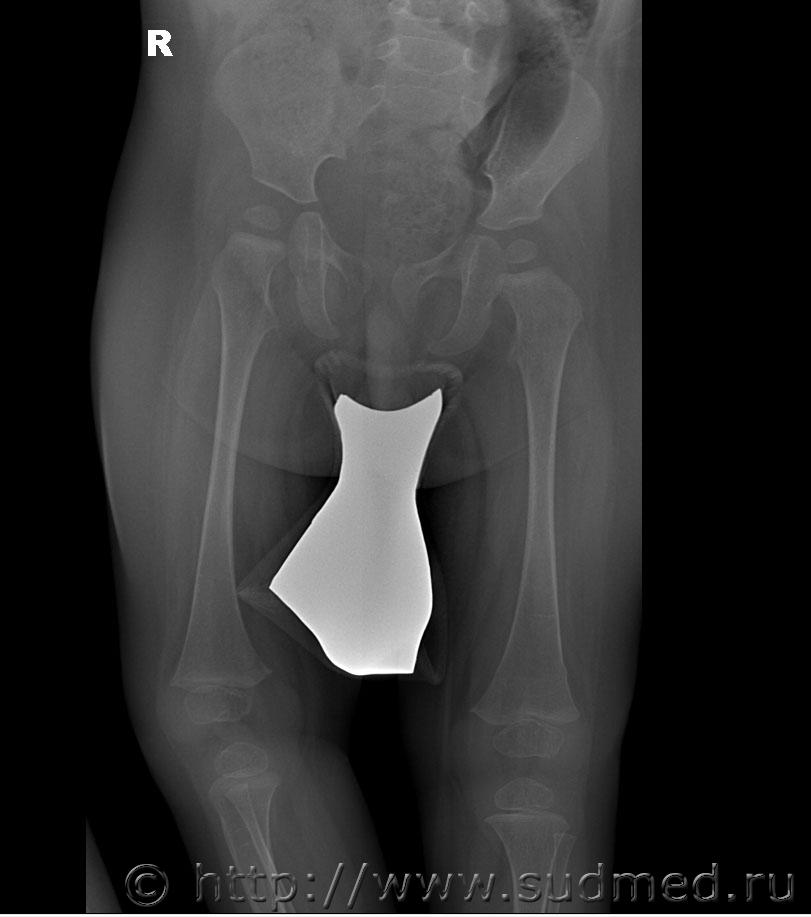

Добрый день, уважаемые коллеги. Нужна помощь в оценке степени тяжести поднадкостничного перелома нижней трети диафиза бедренной кости у ребенка 1 года. Судя по снимкам, перелом вколоченный. По версии следствия, перелом образовался во время массажа, ребенок лежал на животе, со слов массажиста в момент упора ребенка стопами в ладонь врача, при движении вперед в горизонтальном положении ребенок заплакал. В вертикальном положении при упоре стопами в пеленальный стол стал приподнимать больную ногу и плакать. снимки выполнены в тот же день. Рентгенолог изменений структуры кости на снимке не отмечает.

Я рентгенолог не профессиональный и не детский, но перелома не вижу. Ограниченное тяжистое или симметрично-очаговое вспучивание компакты (отторжение надкостницы?) в супракондилярных зонах - местах крепления мышц голени.

Перелом есть. По типу "зеленой веточки", судя по симметричности, действительно вколоченный.

Да. По формальному признаку: перелом диафиза бедренной кости. Легкий или средний вред Мед.критериями всерьез не обосновать.

Это те же снимки, не обрезанные.

Судебная медицина - Прикрепленное изображение Судебная медицина - Прикрепленное изображение

Честно говоря, какого -либо уплотнения губчатого вещества я тоже не вижу, возможно Вы правы по поводу отторжения надкостницы. Но две консультации рентгенологов указывают на перелом. Думаю нужна консультация снимков детским травматологом-ортопедом с привлечением рентгенолога.